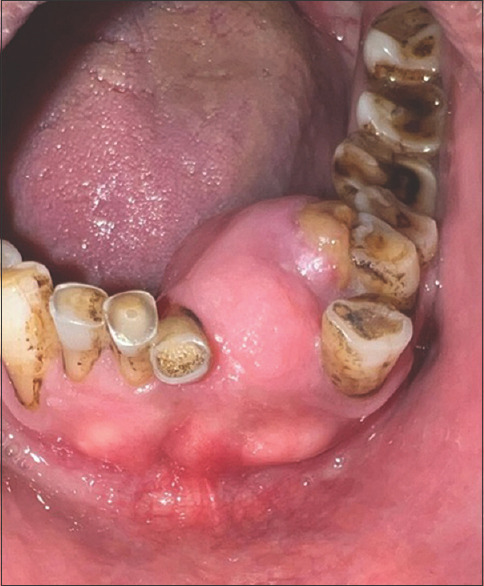

Osteochondroma (OC) is the most common benign tumour of the axial skeleton which often occurs from the metaphysis of the long bones but rarely occurs in the craniofacial region (<1% of cases). Literature shows that cases occur more in the mandibular condylar region. To date, only six cases of this incredibly rare OC in the mandibular front region have been documented in the last 30 years. In addition to reviewing the literature on OCs of the mandibular front region, this case report describes a case of OC involving the mandibular symphysis and left para-symphysis in a 67-year-old male patient. Histopathological examination revealed chondroid and osteoid tissue with sparse fibrous tissue patches and columns of chondrocytes with single tiny nuclei within the cartilaginous cap, and all these features were strongly suggestive of OC diagnosis.